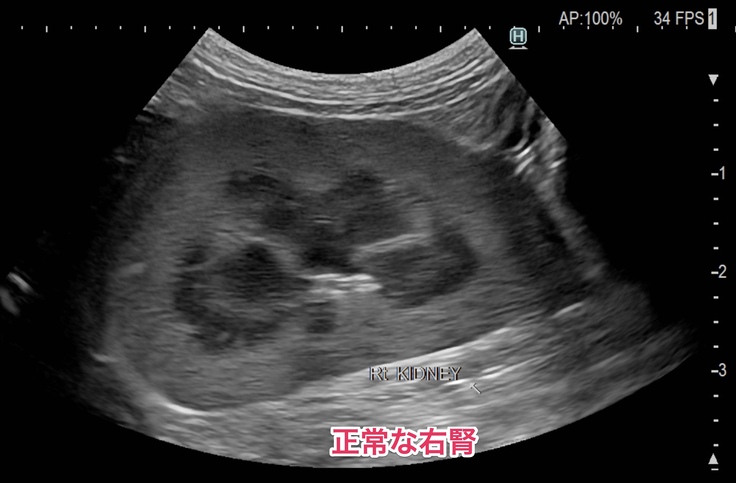

🐈右側の腎盂。左の腎盂のように黒い影が膨らんでいません🐈

今は右側の腎臓と腎盂機能が正常で、機能していない左側の腎臓の分までカバーしてくれているので血液検査でも異常な数値は出なかったけど、右の方も左側と同じように詰まってしまえば腎臓の機能がストップしてしまうので尿毒症や腎不全になったりして食欲不振や嘔吐するようになって体調が良くない日が多くなったり、透析等の別の治療が必要になる場合もあるかなと説明を受けました。